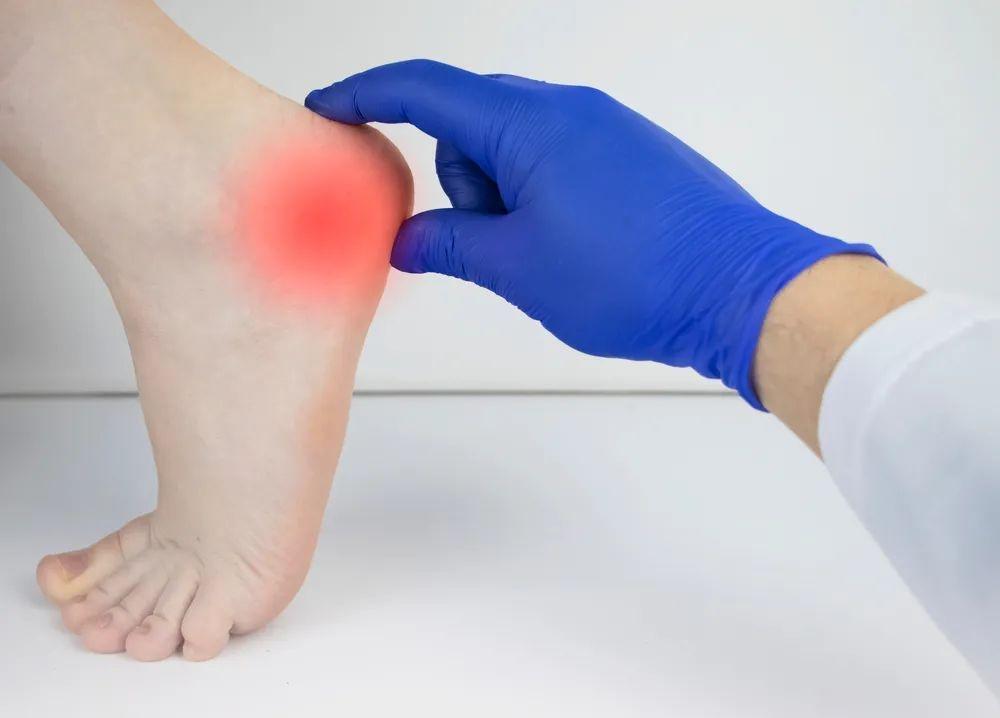

行走时足部特征表现为轻度跖屈及内翻,最常见体征是跟骨结节内侧的局限性压痛,可伴轻微的肿胀及发红。

在足底筋膜炎的患者查体中,Windlass 试验具有 100% 的特异性和 32% 的敏感性,阳性结果为:稳定踝关节时,被动背屈跖趾关节引起足后跟疼痛。